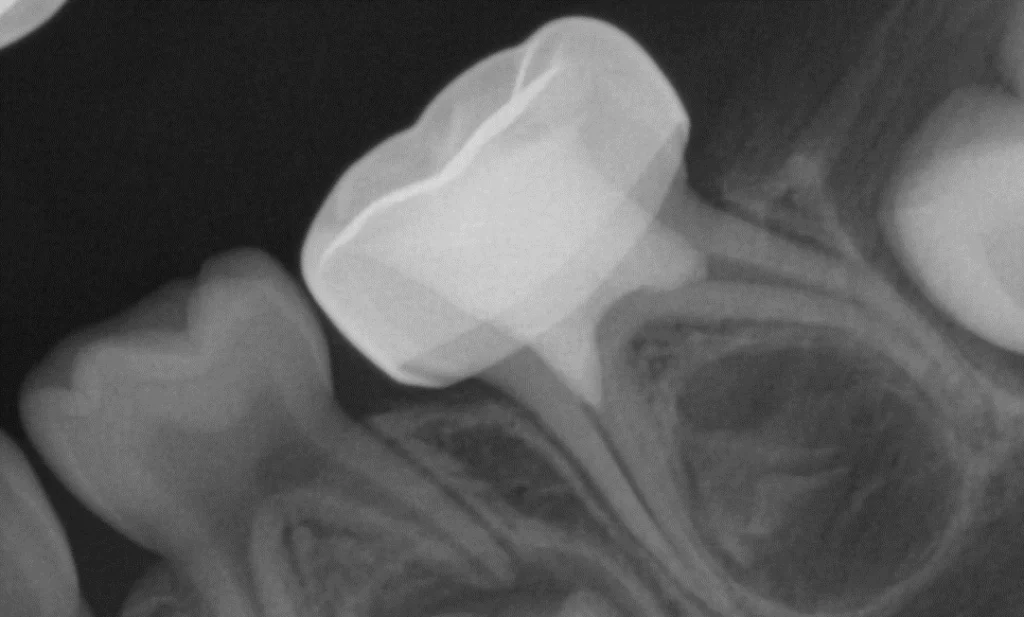

Radiographic Examination in Paediatric Dentistry (1 hour)

Learn proper techniques for taking and interpreting radiographs on paediatric patients, including behaviour management strategies, radiation safety considerations, and diagnostic interpretation specific to the developing dentition.